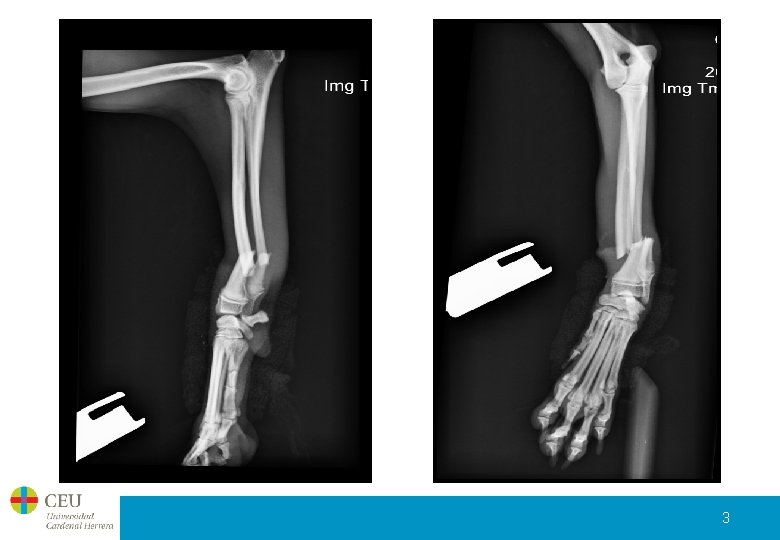

Presentación del caso • Nombre: Cuca • Nº Caso: 09/1470 • Especie: Perro • Raza: Mestizo • Sexo: Hembra • Edad: 7 meses • Peso: 6 kg El paciente no apoya el miembro anterior izquierdo. 2

3

Resolución de la fractura Se decide resolver la fractura con un fijador externo bilateral, con una reducción abierta limitada o mínima. 4